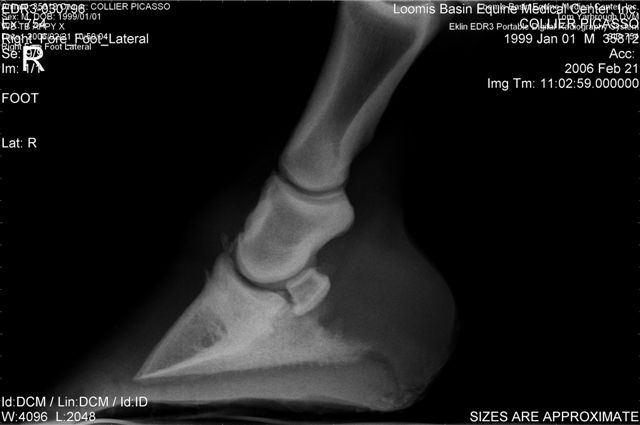

On the right the main problem is the appearance of the n. bone in the first image. It appears to have large irregular areas of increased lucency surrounding areas of decreased lucency. The darker areas (decreased lucency) may be artifacts or represent thinning of cortical bone.

Unless there is something I am missing in the images the extensor process appears to have healed well on the L. The significance of each of these lesions will depend on clinical findings Ann and confirmation that these are actual lesions and not artifacts created by positioning or the foot preparation for radiography. You should note I am not a radiologist and that viewing images in this manner is not as revealing as viewing the radiographs first hand.

The low heels are certainly the one thing you can address but also squaring the toes would decrease strain on the navicular region and they do look long in the images.

No I don't think squaring will put more stress on the extensor process and the R looks pretty well aligned. Concerning the R navicular bone see my comment above.

DrO